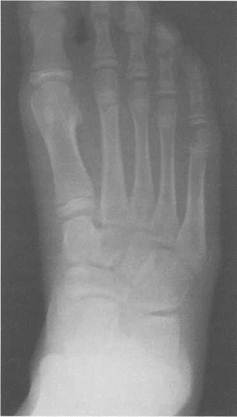

Рис. 19.140. Рентгенограмма стопы (6 лет).

1— таранная кость; 2 — пяточная кость; 3 — кубовидная кость; 4 — ладьевидная кость; 5 — клиновидные кости; 6 — эпифиз I плюсневой кости; 7 — эпифизы IV и V плюсневых костей.